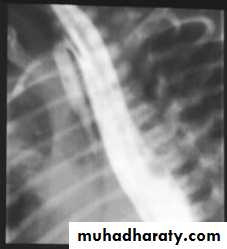

-- Barium study

Presentation :-Polyhydraminous.Frothy secretion.Respiratory distress.Resistance to NG tube insertion.Plain X-ray.